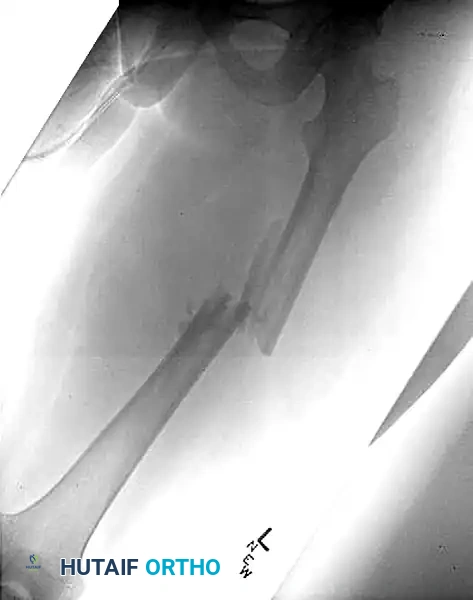

Figure 55-62A: Preoperative radiograph demonstrating a displaced ipsilateral femoral neck and shaft fracture.

Figure 55-62B: Postoperative radiograph demonstrating fixation of the femoral neck with cannulated screws and the shaft with a retrograde intramedullary nail.

Figure 55-62C: Lateral postoperative radiograph confirming anatomic alignment and appropriate hardware placement.